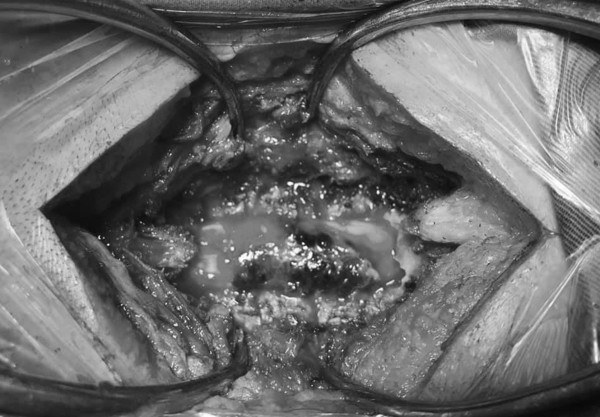

Ca mổ cấp cứu cho bệnh nhân được tiến hành lúc gần nửa đêm và kết thúc sau đó 2 tiếng, khối máu tụ lớn trong cột sống cổ của bệnh nhân được lấy bỏ, giải phóng chèn ép tuỷ thần kinh.

Khối máu tụ (màu đen) chèn ép tủy đố sống cổ